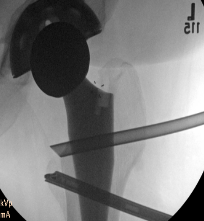

Use image intensifer to triangulate to lesser tuberosity

Psoas tendon Diathermy release Cleared lesser tuberosity